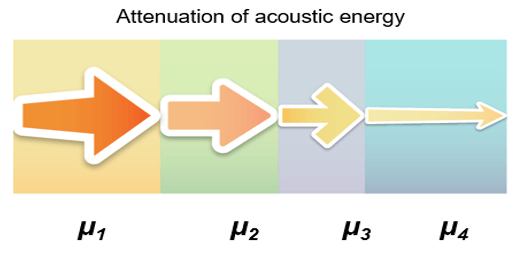

The amplitude and intensity of ultrasound waves decrease as they travel through tissues. Theoretically, the attenuation coefficient (μ) in soft tissues, is almost proportional to the ultrasound frequency and depth, with a range between 0.5 and 1 dB / (MHz.cm).

The attenuation is one of the parameters that limit the maximum frequency. It is important to note that lowering the frequency improves the depth of exploration because the ultrasound attenuation primarily increases with frequency. The maximum depth of exploration with a center frequency of 20 MHz is approximately 6-10 mm.